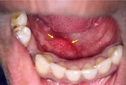

Çene altında beze oluşumu beni oldukça rahatsız etti. İlk başta küçük bir nodül gibi görünüyordu, fakat zamanla büyüyüp ağrılı hale geldi. Dermatologa başvurduğumda hidradenit suppurativa tanısı kondu. Tedavi sürecim devam ediyor, umarım en kısa zamanda iyileşirim.

Beze, tıpta "hidradenit suppurativa" olarak bilinen, genellikle ciltte iltihaplı nodül ve apselerin oluşumuyla karakterize bir hastalıktır. Bu durum, özellikle ter bezlerinin yoğun olduğu bölgelerde, yani koltuk altı, kasık, kalça ve meme altı gibi yerlerde meydana gelir. Beze, genellikle ciltte ağrılı lezyonlar, iltihap ve kötü bir koku ile birlikte seyreder. Bu makalede, bezelerin belirtileri, tanı yöntemleri ve tedavi seçenekleri detaylı bir şekilde ele alınacaktır. Beze BelirtileriBeze belirtileri genellikle aşağıdaki şekilde sıralanabilir: